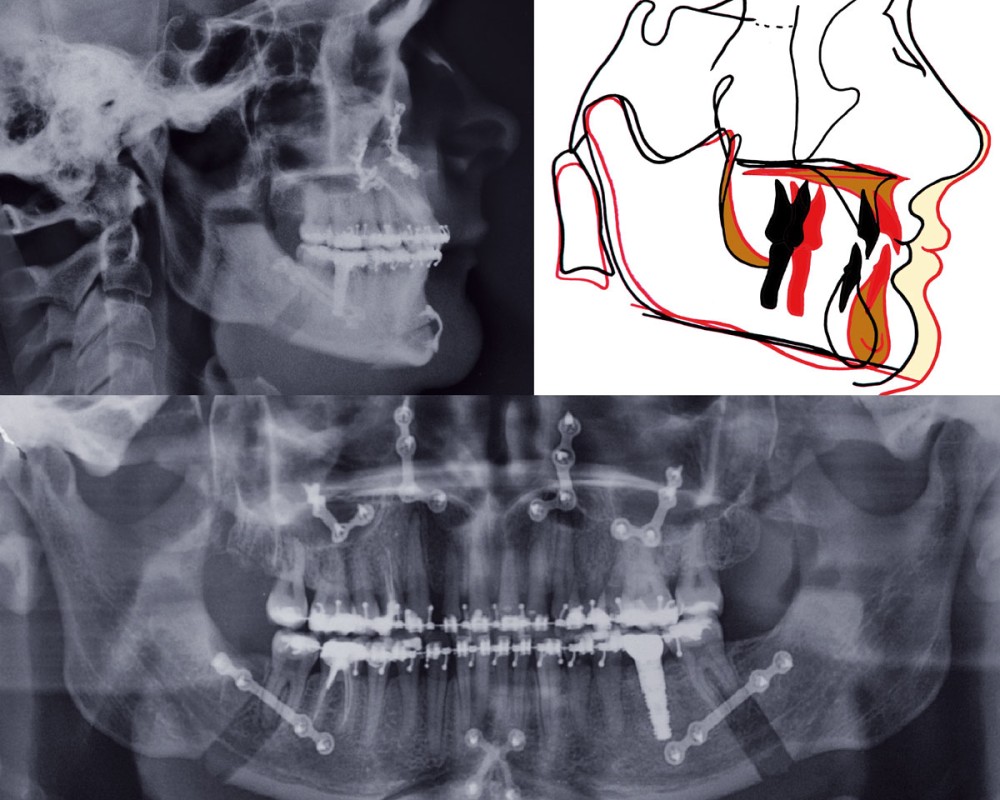

Cette patiente âgée de 39 ans, désireuse d’améliorer son sourire et son confort articulaire mandibulaire, nous est adressée par son chirurgien-dentiste le Dr S. Felenc. En effet, ce dernier ne peut proposer une réhabilitation cosmétique du guide incisivo-canin fonctionnelle, pérenne et non mutilante, sans orthodontie. Comme il l’explique dans une précédente publication, sur cette situation clinique, la phase prothétique doit être aussi économe que possible du point de vue tissulaire (1). Et ici, le faible espace prothétique disponible lié à la classe II division 2, la forte abrasion et la faiblesse amélodentinaire sont associés à un désordre plus global des bases osseuses.

Cette patiente présente toutes les caractéristiques d’une classe II division 2 primitive dont l’empreinte génétique s’exprime par une hypodivergence mandibulaire sévère sans réel décalage sagittal, mais avec un important développement basal antérieur du corpus mandibulaire et cette forte projection symphysaire caractéristique. De plus, on retrouve « le syndrome de petites dents dans de larges maxillaires » décrit par Peck et al (2).

Le préjudice esthétique vient de la concavité du profil accentuée par la profondeur nasale, l’ouverture de l’angle naso-labial et la proéminence du menton. Les lèvres sont fines et tendues. L’inclinaison vestibulo-linguale, le recul et la petitesse des dents ne soutiennent pas les lèvres lors du sourire de profil. De plus, le sourire est gingival et laisse apparaître le torque radiculo-vestibulaire excessif des incisives et des canines maxillaires, d’où leur peu d’éclat, aggravé par des restaurations au composite (fig. 1a-c et 2).

Les dents sont d’autant plus soumises à l’hypertonicité de l’enveloppe musculaire tant élévatrice que labio-jugale…